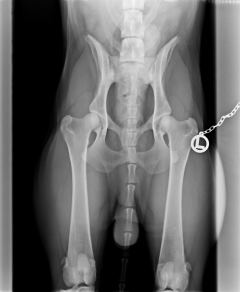

Bayou ist HD frei, ED frei und OCD frei.Beste Vorraussetzung für ein Deckrüde.

HD                                                           ED-Rechts                                         ED-Links                                                 OCD-rechts                                            OCD-links